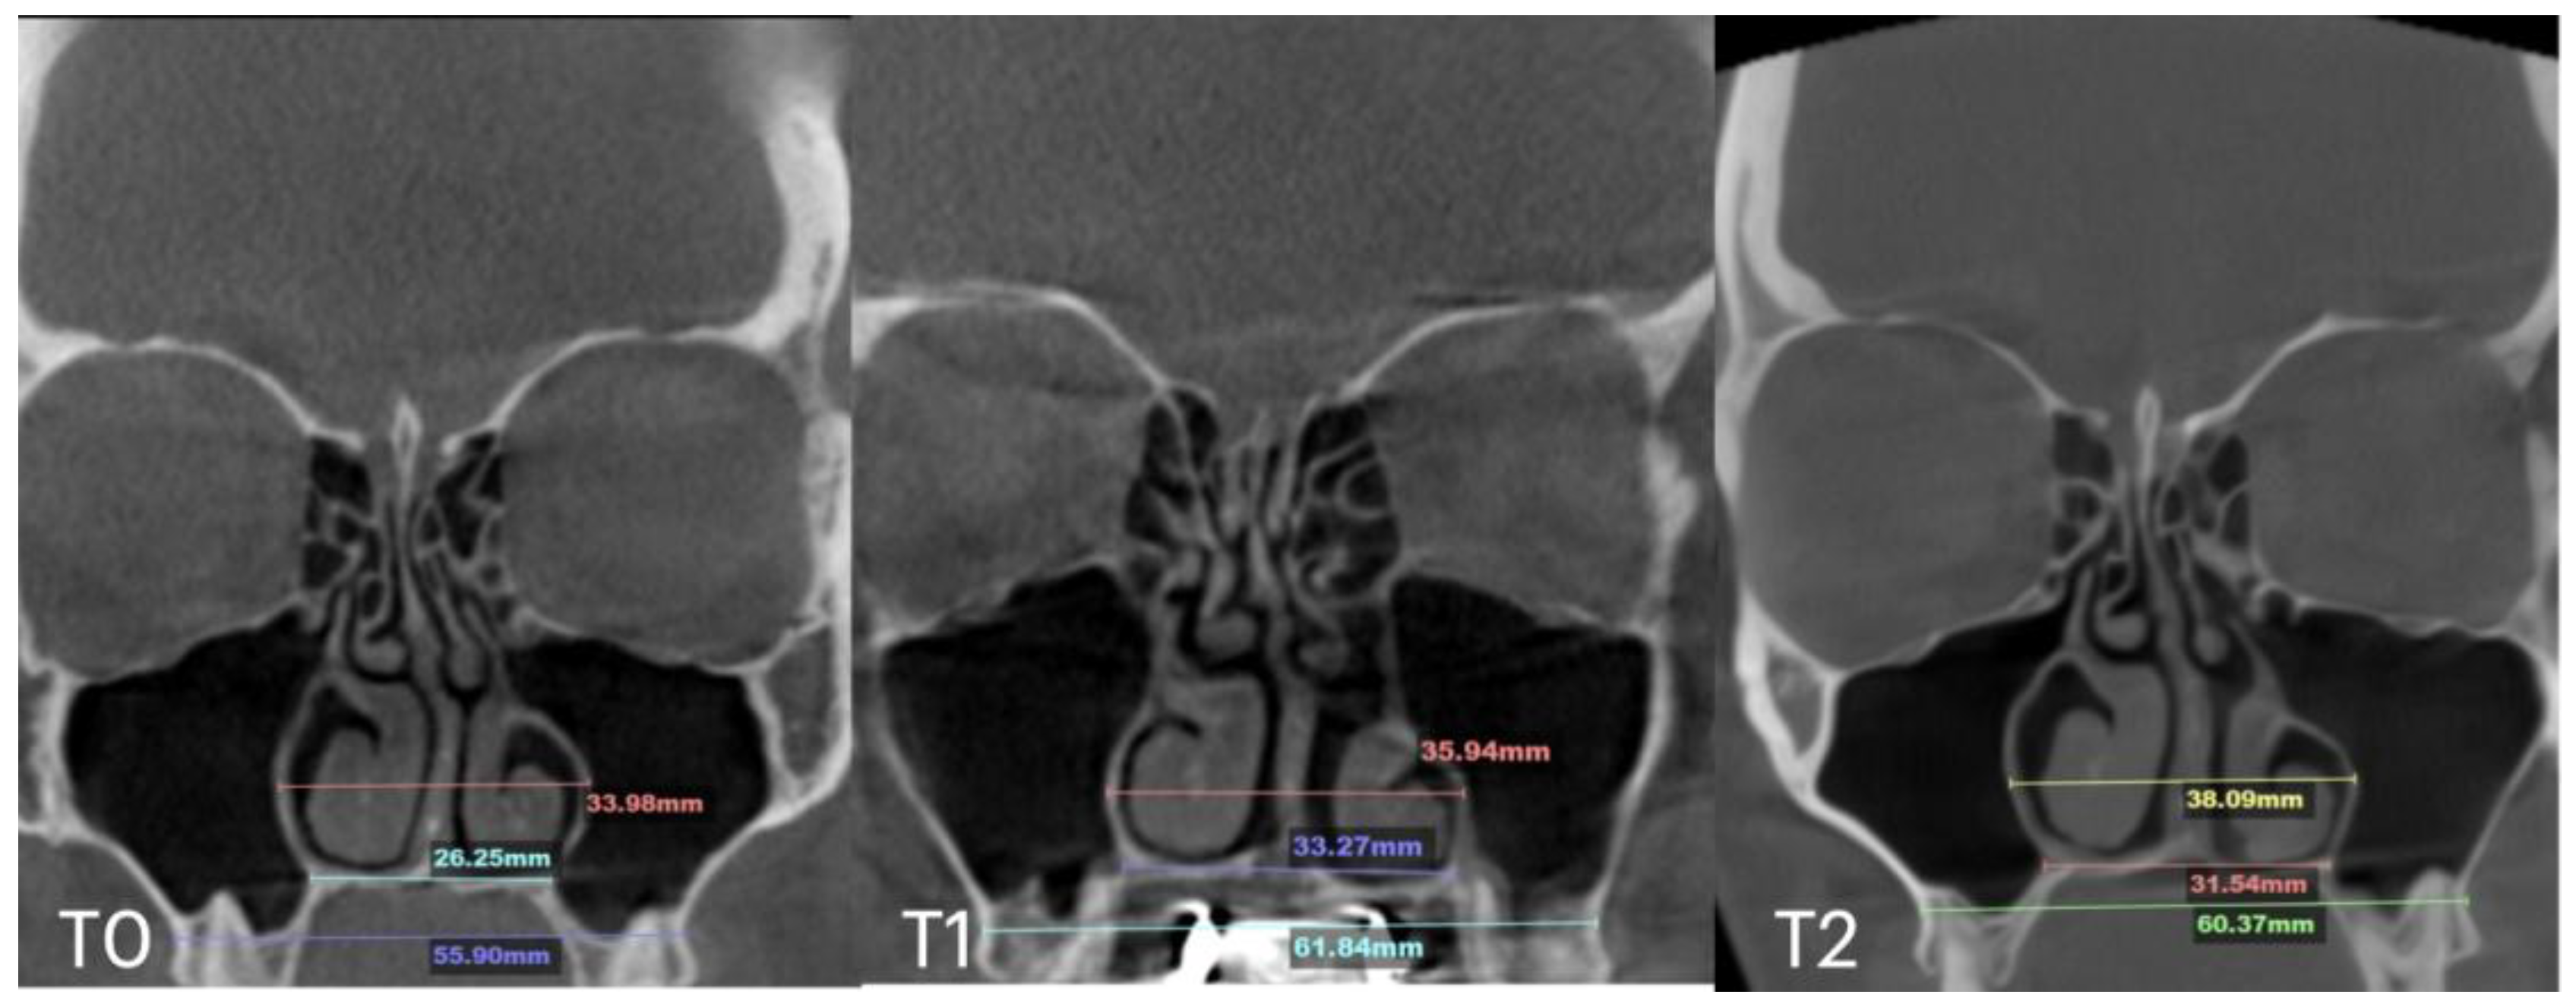

2.7. Case D: Midfacial Asymmetry Correction with Guided Expansion

| Nasal Base Width, mm | Maxillary Base Width, mm | Lateral Nasal Width, mm | Inter-Pterygoid Distance, mm | Midpalatal Suture Separation, mm | |||||||||

|---|---|---|---|---|---|---|---|---|---|---|---|---|---|

| T0 | T1 | T2 | T0 | T1 | T2 | T0 | T1 | T2 | T0 | T1 | T2 | T1 | |

| Case A | 30.84 | 38.15 | 38.37 | 59.22 | 66.37 | 67.11 | 32.8 | 39.33 | 39.48 | 28.01 | 32.88 | 33.38 | 10.5 |

| Case B | 30.61 | 34.41 | 34.97 | 59.73 | 63.47 | 60.56 | 31.79 | 34.6 | 35.35 | 29.18 | 31.38 | 34.59 | 5.7 |

| Case C | 28.40 | 38.32 | 36.72 | 53.63 | 62.43 | 59.80 | 31.29 | 38.45 | 38.51 | 29.15 | 35.8 | 35.36 | 8.47 |

| Case D | 26.25 | 33.27 | 31.54 | 55.9 | 61.84 | 60.37 | 33.98 | 35.94 | 38.09 | 29.77 | 29.24 | 29.02 | 6.2 |